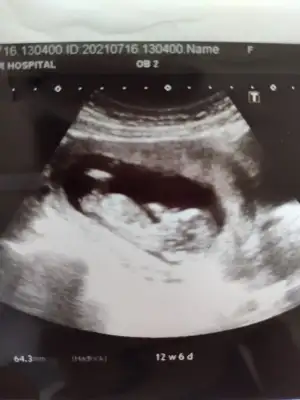

Yas riski tek basina birsey anlam ifade etmiyormus

Allah bağışlasın, evladınız sağ selamet kolaylıkla kucagınıza alın inşallah gözünüz aydın![]()